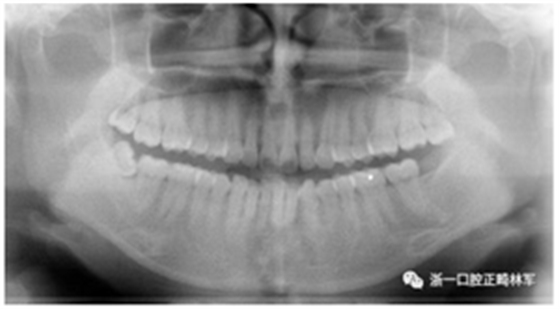

初診全景片:牙齒數(shù)目形態(tài)未見異常,牙根未見異常。48近中阻生。